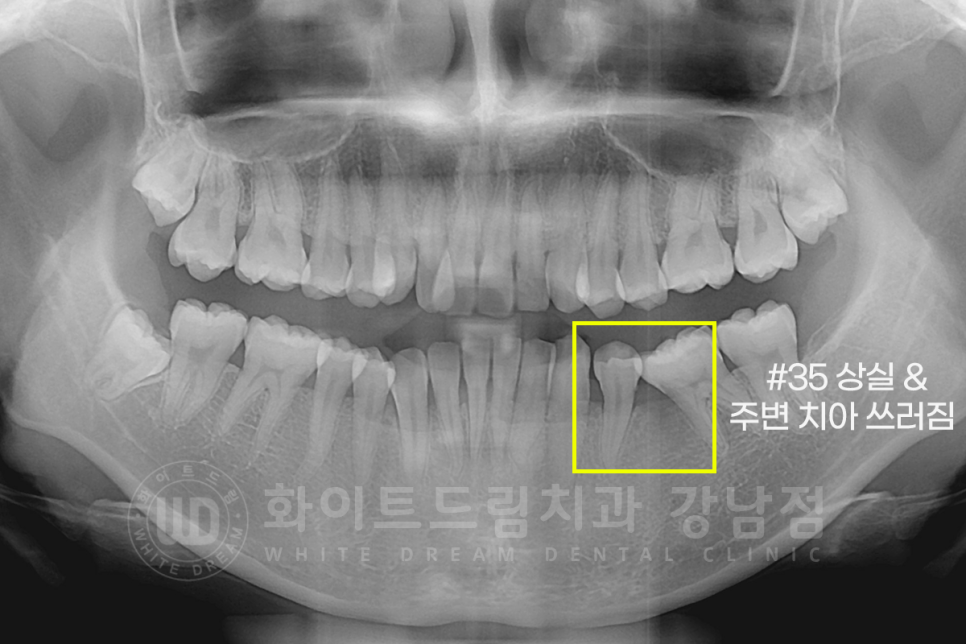

덧니(crowding)이 심하신 상태 + 35번 치아가 상실된 상태로 본원을 찾아주신 환자분의 케이스 리뷰입니다.

치아의 틀어짐 외에도 문제가 하나 더 있었는데요.

35번 치아가 상실되었고, 상실된 지 시간이 오래되어 주변 치아들이 다 쓰러진 상태였습니다.

그리고 골 소실도 심한 상태였죠.

우선 임플란트를 식립할 공간이 없기 때문에,

전체 치아교정을 통해 임플란트 식립 공간 확보와 전체 치열을 고르게 만들기로 했습니다.